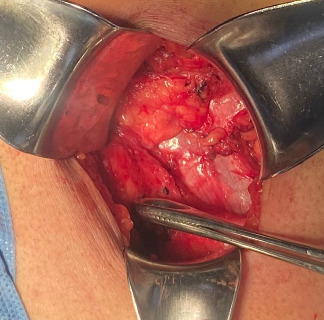

背景:Grynfelt 腰疝是所有腹壁疝中最罕见的一种,占病例的 1.5% 到 2%,迄今为止仅描述过 300 到 350 例。腰疝可以是先天性的,也可以是后天性的,通常由外伤或手术(先天性)引发。诊断依据临床表现,并通过计算机断层扫描确诊。需要进行手术治疗,通过开腹或腹腔镜手术进行修补。材料与方法:本病例为一名年轻女性,既往无手术史,也无外伤史,诊断为 Grynfelt 疝。手术结果患者接受了选择性左腰部切除手术,并使用腹膜上聚丙烯网片进行了疝成形术。术后恢复良好,术后 4 小时即可出院。普外科门诊分别在 20 天、1 个月、3 个月和 6 个月进行了随访,没有发现复发、并发症或事故。结论Grynfelt疝是一种罕见病,需要高度怀疑才能准确诊断。虽然病例通常没有症状,但未经治疗的疝气可导致严重的发病率。早期识别和及时手术治疗对于缓解症状和预防并发症至关重要。在本病例报告中,手术治疗包括通过左腰部切开术进行疝成形术,修补疝缺损并缩小疝内容物。为确保充分闭合,还放置了上腹膜网片。鉴于这种病症的罕见性,文献中没有具体的治疗指南。因此,这种类型的修补术是根据术中发现决定的。需要进一步开展研究,以明确管理策略,优化 Grynfelt 疝患者的治疗效果。

Background: Grynfelt's lumbar hernia is the rarest of all abdominal wall hernias, accounting for between 1.5% and 2% of cases, with only 300-350 instances described to date. Lumbar hernias can be congenital or acquired, often triggered by trauma or surgery (iatrogenic). Diagnosis is clinical and confirmed via computed tomography. Surgical intervention is required for resolution, with repair performed either through open or laparoscopic surgery. Material and Methods: We present the case of a young female with no prior surgical or traumatic history, in whom the diagnosis of Grynfelt's hernia was made. Results: The patient underwent elective left lumbotomy surgery with hernioplasty using a supra-aponeurotic polypropylene mesh. Postsurgical recovery was adequate, and she was discharged 4 h after surgery. Follow-up in the general surgery outpatient clinic occurred at 20 days, 1, 3, and 6 months, with no recurrence, complications, or incidents. Conclusion: Grynfelt's hernia is a rare entity that requires a high index of suspicion for accurate diagnosis. Although cases are often asymptomatic, untreated hernias can lead to significant morbidity. Early recognition and timely surgical intervention are crucial for symptom relief and prevention of complications. In this case report, surgical management involved hernioplasty through a left lumbotomy approach, repairing the hernia defect and reducing the hernia content. Supra-aponeurotic mesh was placed to ensure adequate closure. Given the rarity of this pathology, no specific management guidelines exist in the literature. Therefore, the decision for this type of repair was based on intraoperative findings. Further research is needed to clarify management strategies and optimize outcomes for patients with Grynfelt's hernia.